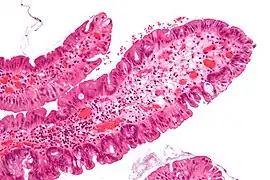

| Tubulovillous adenoma | 20% to 25%[18] | 25%-75% villous[17] |

| |

The villous subdivision are associated with the highest malignant potential because they generally have the largest surface area. (This is because the villi are projections into the lumen and hence have a bigger surface area.) However, villous adenomas are no more likely than tubular or tubulovillous adenomas to become cancerous if their sizes are all the same.[21]

Micrograph of a villous adenoma. These polyps are considered to have a high risk of malignant transformation. H&E stain. -